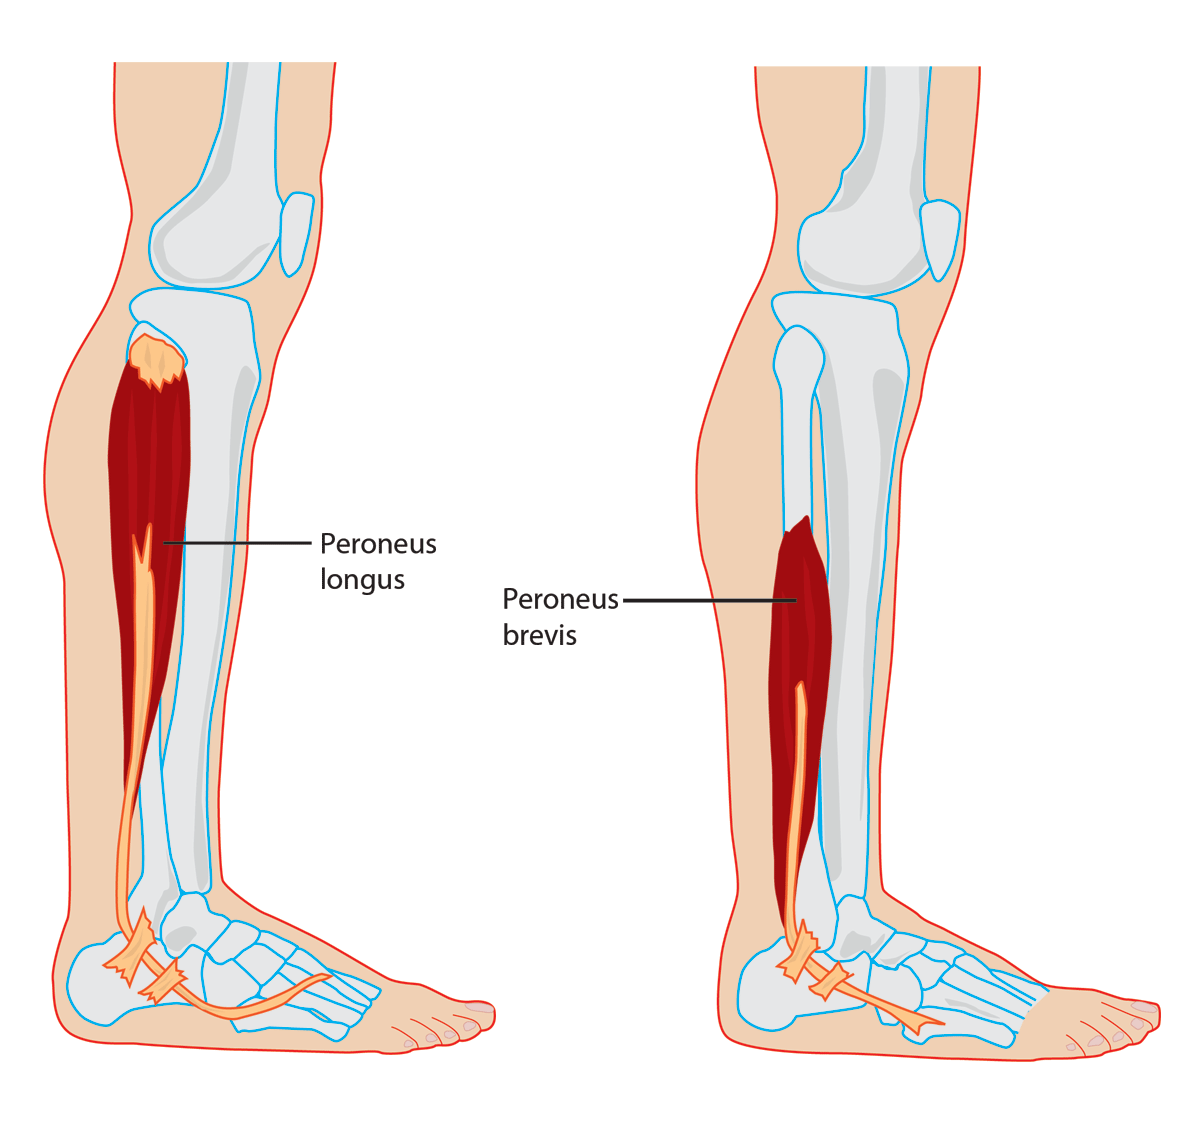

Explain why ankle plantar flexion is only weakened, not absent, in achilles tendon rupture

Peroneal muscles still intact and contribute to plantar flexion